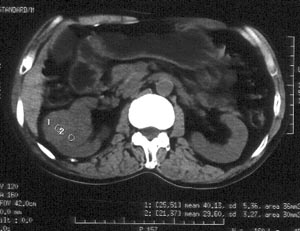

男性,56岁。右腰部不适2月。无血尿,无尿频尿急尿痛。b超提示:右肾下极占位。

ct平扫加增强扫描:右肾中下极肾盂外侧段实质见分叶状软组织密度肿块,截面大约56x45mm,向外突破肾包膜,向内突入肾盂,平扫密度略不均,ct值32-37hu。c+见病灶不均匀轻-中度强化,内有未强化坏死区。右侧肾周筋膜增厚,右肾内前方见肿大淋巴结。

ct诊断:右肾癌,ct表现见上述,伴同侧腹膜后淋巴结转移。